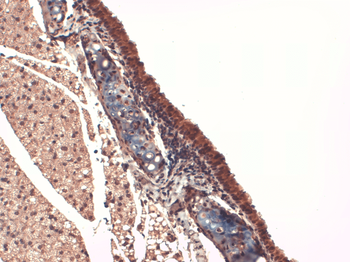

应用稀释比例:WB (1:1000), IHC (1:1000)

应用注释:1 µg/ml of SMC-391 was sufficient for detection of hNIS in 20 µg of transfected COS-7 cell membrane lysate by ECL immunoblot analysis using Goat anti-mouse IgG:HRP as the secondary antibody.